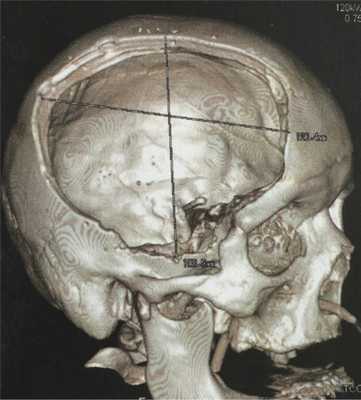

В послеоперационном периоде в неврологическом статусе отмечена медленная положительная динамика. Больная переведена в нейрохирургическое отделение. 05.12.14 состояние осложнилось развитием острого переднего трансмурального инфаркта миокарда с фибрилляцией предсердий, что потребовало перевода в отделение кардиореанимации и соответствующей терапии. До 09.12.15 больная находилась в отделении кардиореанимации. После стабилизации гемодинамических показателей переведена в отделение неврологии, где проводились реабилитационные мероприятия. Выписана из стационара 22.12.14 с рекомендациями. На момент выписки: легкий левосторонний гемисиндром и недостаточность III нерва справа. Ходит в манеже. Обслуживает себя самостоятельно. По поводу костного дефекта рекомендована отсроченная краниопластика (рис. 2).

Рис. 2. Спиральная К.Т.: костный режим с реконструкцией. Визуализируется обширный костный дефект справа.